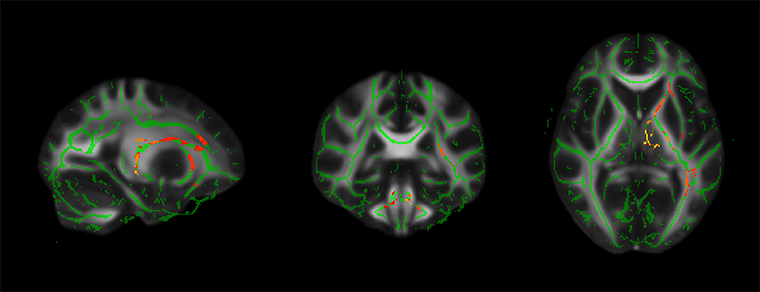

▲PM2.5降低幅度越大與大腦顯著相關的區域,紅黃色為統計顯著區域。(圖/國立陽明交通大學提供)

研究團隊發現,細懸浮微粒與二氧化氮濃度減少與老年人的注意力提升呈正相關。更重要的是,磁振造影顯示這些污染物濃度下降,與多個掌管注意力與記憶力的大腦白質區域結構完整性有密切相關。